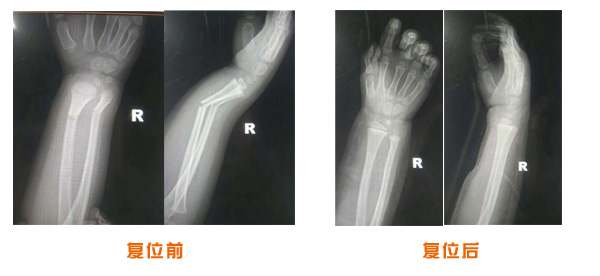

肥城市安駕莊梁氏骨科醫(yī)院是一所以梁氏手法正骨配合膏藥為特色的現(xiàn)代化專科醫(yī)院。

梁氏骨科術(shù)始創(chuàng)于清雍正年間,歷經(jīng)八代,至今已有三百年歷史。據(jù)1929年泰安縣志載“梁瑞圖先生,字增生,號蓮峰,安駕莊人,精岐黃并發(fā)明接骨,凡跌打車凡跌打車軋皮不破而碎骨者......【詳細】 |